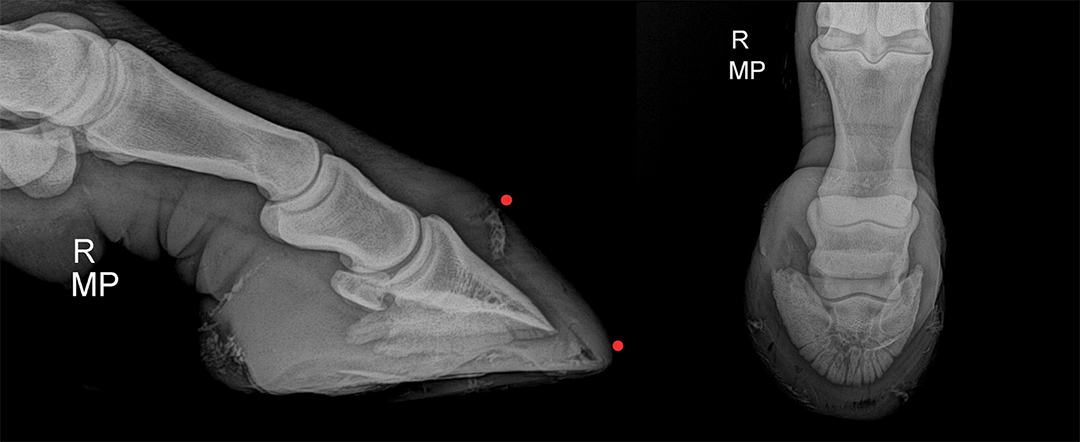

Radiographic studies were performed to rule out infection in the hoof of the forelimb, due to a horseshoe nail that was in sensitive tissue and, when removed, released purulent material. The hoof was cleaned and poulticed to drain infection. The radiograph showed a tract from the white line to the coronary band of the right fore hoof, but no involvement of the pedal bone (fig 4).

Figure 4 Radiograph of right fore showing damage (orange dots, left) in the toe and coronary band (right) following a nail puncture